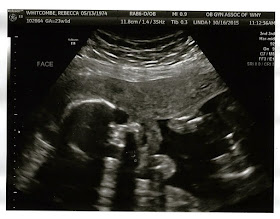

Feel like a broken record and the images are almost the same but can tell little by little he's getting bigger and bigger. Top pic is 3D image his little hands are in front of his face. Fluid was good, still lower than the normal but is getting more consistently up.